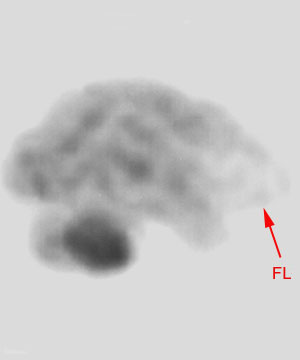

On nuclear SPECT cerebral perfusion images, one may see hypoperfusion defects in the ventromedial frontal region in the frontal variant of Frontotemporal dementia. In the temporal lobe variant of Frontotemporal dementia, SPECT demonstrates hypoperfusion in one or both temporal lobes and anterolateral temporal lobe atrophy involving the polar region, fusiform, inferolateral gyri with sparing of the hippocampal formation may be manifested. Invariably the left temporal lobe is more affected than the right temporal lobe. |

![]() ![]() Both images above are SPECT images using Tc-99 in an individual with Pick's disease. |